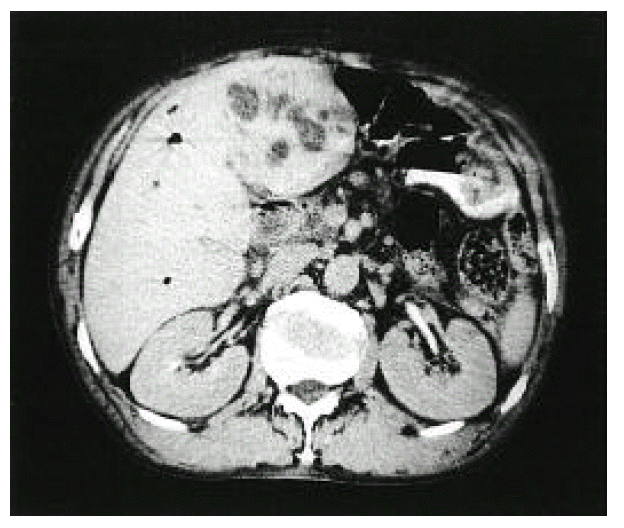

Figure 1.

Abdominal CT showing 7×5 cm sized multiple separated lower density lesion in medial segment of left hepatic lobe.

A 66-year-old man was admitted to Keimyung University Hospital because of decreased urine output and right upper quadrant pain. Seven years earlier, he had a Whipple’s operation for obstructive jaundice due to Ampulla of Vater cancer. At that time, the pathology report showed a moderately differentiated adenocarcinoma and biopsies of the regional lymph nodes showed no evidence of metastasis. At that time, renal function was normal and the urine contained no proteins or red cells. Two weeks before admission, the patient developed right upper quadrant dull pain, nausea, anorexia, myalgia, chills and fever. Four days prior to admission, he noticed gross hematuria, marked decrease in urine output and edema in lower extremities. On admission, his body temperature was 36.4°C and blood pressure was 110/60 mmHg. Daily urine output ranged 800–1200 mL. Face was puffy. He did not have icterus. His conjunctivae was slight anemic and revealed several petechial hemorrhages. Auscultation of the lung revealed bilateral basilar rales. No murmurs or frictions were heard. The liver was enlarged and tender. There was no splenomegaly or rash. There was marked costovertebral angle enderness. here was mild pretibial edema. Laboratory data on admission showed WBC 34,600/mm3, hemoglobin 8.3 g/dL, platelet count 95,000/mm3, BUN 16.4 mmol/L, serum creatinine 985,6 μmol/L, cholesterol 118 mg/dL, total bilirubin 3.4 mg/L, alkaline phosphatase 270 IU/L, SGPT 18 IU/L, and serum albumin 2.0 g/dL and creatinine clearance 2.5 ml/min. Urinalysis showed specific gravity 1.020, protein 2+, and urinary sediment containg two granular casts, many red blood cells and 10 white blood cells/HPF. The 24-hour urinary protein excretion was 2.4 gm and FENa was 1.7%. C3 level was 0.67 g/L (normal range: 0.8–1.2 g/L) and C4 level was 0.46 g/L (normal range: 0.2–2.5 g/L). Cryoglobulin was absent. The tests for hepatitis B and C, antinuclear antibody and rheumatoid factor were negative. Chest radiographs demonstrated bilateral perihilar pulmonary congestions. On admission, he was afebrile. He had obvious pulmonary edema as well as peripheral edema. Immediate hemodialysis resulted in a weight loss of 2 kg and respiratory improvement. Ultrasonographic examination of liver showed ill marginated cystic mass in left lobe. Computed tomography (CT) of the abdomen demonstrated 7×5cm sized multiple septated lower density lesions in medial segment of left lobe of the liver (Figure 1). Numerous blood cultures were negative. Initially the patient was treated with diuretics, albumin infusions and antibiotics (sulbactam/cefoperazone and aztreonam). On the 15th day, percutaneous needle biopsy of the kidney was performed. Light microscopy showed 17 glomeruli with two global sclerosis. The glomeruli showed endo-and extracapillary proliferation (Figure 2), with cellular crescents involving 25% of the glomeruli. The interstitium showed diffuse edema and no tubular necrosis. Immunofluorescent examination showed a diffuse granular staining with anti-IgG and anti-C3 along the capillary wall, and no staining with anti-IgM or anti-IgA (Figure 3). Needle aspiration of the liver was performed on the 19th hospital day, with the drainage of greenish pus material. Culture of the liver aspirates later grew Pseudomonas aeruginosa. Ticarcillin was given. The patient improved substantially. The levels of BUN and serum creatinine declined progressively and stabilized at 5.7 mmol/L and 176 μmol/L, respectively, by the 25th hospital day. One month after admission, the laboratory findings were : BUN 5.5 mmol/L, serum creatinine 176 μmol/L, hemoglobin 8.1g/dL. WBC 5,430/mm3 and platelet count 208,000/mm3. The 24-hour urinary protein excretion was 4.4 g/day. Follow-up CT showed almost complete resolution of previous abscess in the liver. He was discharged on the 40th hospital day with the serum creatinine level of 167 μmol/L.